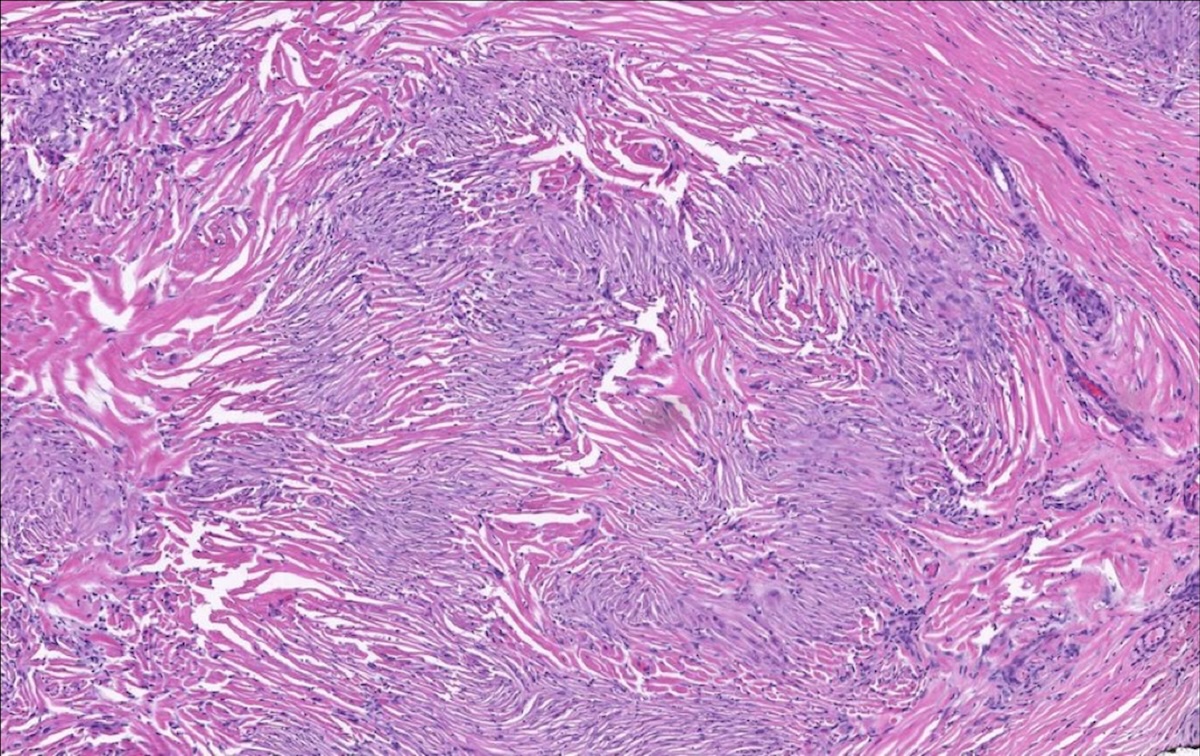

Buenas tardes. Este caso fue reportado como: ERITEMA ELEVATUN DIUTINUM (Vasculitis Fibrosante)

El eritema elevado persistente (EEP), o eritema elevatum diutinum, es una dermatosis crónica infrecuente caracterizada por pápulas, placas y nódulos de color de rojo violáceo a rojo castaño que muestran predilección por las superficies extensoras. Los hallazgos histopatológicos consisten en una VLC en las lesiones tempranas seguida de una sustitución fibrótica de la dermis en las lesiones más antiguas.

Este caso presentaba nódulo rojizo en los codos.